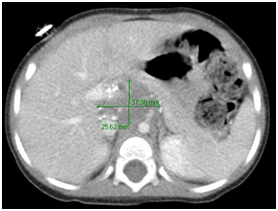

14month old female with a history of stage III neuroblastoma, no other comorbidities, presented to our institution for a left thoracoabdominal exploration and resection. As the surgeon made preparations to close, the patient’s SBP’s almost immediately decreased from 90’s (general trend) to 60’s mmHg, accompanied by an elevation in heart rate. Several 20 cc/kg boluses of isotonic crystalloid fluid were administered with no change in hemodynamics. A dopamine infusion was started for refractory hypotension. Surgical exploration revealed the small bowel to be diffusely dusky and ischemic; the surgeon identified a thrombus in the superior mesenteric artery (SMA) (Figure 2 & 3).1˗3 An ABG returned with a pH 7.047 in the setting of profound lactate acidosis with a lactate of 10.4 mmol/L. Vascular surgery was consulted for an SMA embolectomy and heparin 250 units IV was given. As the case progressed, dopamine was up-titrated to maintain MAPs > 40mmHg. The patient’s lactate continued to rise in spite of reperfusion to the SMA, leading to significant vasoplegia and requiring the addition of an epinephrine infusion. A Whipple procedure was performed and the patient was closed, left in discontinuity. She was transported to the PICU intubated, on dopamine and epinephrine infusions.

Figure 3 ICT abd/pelvis: 3.8 x 2.6 cm partially calcified heterogeneous paravertebral mass, encases celiac and superior mesenteric arteries and left renal vein, and partially encases the renal arteries.